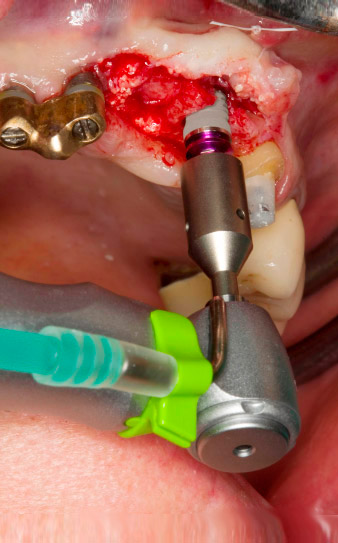

Taraudage avec le contre-angle WS-75 L

Fig. 3 : Taraudage avec le contre-angle WS-75 L suivant un ratio de 20:1 (programme P4). Le couple élevé de l'Implantmed, son système de serrage hexagonal pour une transmission de puissance fiable et l'inversion automatique du sens de rotation lorsque la résistance est trop élevée s'avèrent être des caractéristiques particulièrement utiles ici.